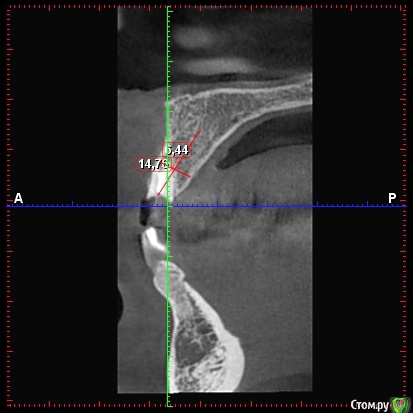

колесников Опубликовано 21 марта, 2018 Поделиться Опубликовано 21 марта, 2018 Можно,но не нужно. Размеры оптимальные. Немедленная нагрузка показана. Стремитесь к винтовой фиксации,длинный Имплант в этом случае будет сложно расположить. Удалять атравматично,лоскут не откидывать, Сст вестибулярно 1 Ссылка на комментарий

Irouil Опубликовано 21 марта, 2018 Поделиться Опубликовано 21 марта, 2018 (изменено) Почему тут 3.6*12 не войдёт? По моему на винтовую выводится. 10мм тоже норм, но для немедленной нагрузки 2мм лишними будут? Изменено 21 марта, 2018 пользователем Irouil 1 Ссылка на комментарий

колесников Опубликовано 21 марта, 2018 Поделиться Опубликовано 21 марта, 2018 (изменено) Чтобы отвертка не уперлась в режущий край,ставить лучше более вертикально,Апекс в этом случае будет близко к вестибулярной компактной пластинке ,после нагрузки может быть окончатся резорбция. Мне кажется, 10 мм с заглублением, самое то. Изменено 21 марта, 2018 пользователем колесников 1 Ссылка на комментарий